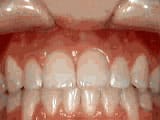

Crowding of the teeth

Before

AfterThis boy started treatment at age 11 and wore braces for 26 months. He loves his new smile.